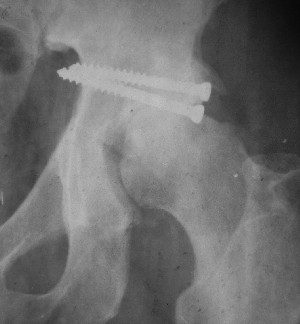

Считаю, что в представленном Вами случае целесообразно подумать о первичном протезировании. Привожу пример более легкого повреждения, где потерял время надеясь спасти сустав.

Больной 18 мая 2003 года в автоаварии получил перелом левой вертлужной впадины, вывих бедра. Госпитализирован в один из стационаров области.Вывих вправлен. В последствии бедро вывихивалось еще дважды. На консультацию был представлен снимок от 19.05.03г., больной переведен к нам 3.06.03г. Снимок при поступлении - перелом впадины, задне-верхний вывих бедра. 05.06.2003 г. выполнено открытое вправление вывиха левого бедра и остеосинтез стенки вертлужной впадины двумя винтами. Послеоперационный период без осложнений. Объем движений в левом тазобедренном суставе восстановился полностью. Выписан на амбулаторное лечение в удовлетворительном состоянии с рекомендациями 3 месяца ходить на костылях без нагрузки на оперированную конечность. На контрольных рентгенограммах левого тазобедренного сустава 13.10.2003 г. - признаки консолидации перелома; плотность, форма головки и состояние суставных поверхностей удовлетворительные. Разрешена дозированная осевая нагрузка, на конечность с использованием дополнительной опоры. 19.12.2003 г. больной обратился с жалобами на боли в левом тазобедренном суставе. На рентгенограммах левого тазобедренного сустава 19.12.2003 г., 20.02.04г. - асептичекий некроз головки бедра. 5.04.04г. - эндопротез. Сейчас ходит без трости, не хромает. Особенность эндопротезирования - при удалении винтов прослежена линия перелома заднего края впадины и предложено установить чашку несколько меньшего диаметра, чтобы она была покрыта несломанной частью.